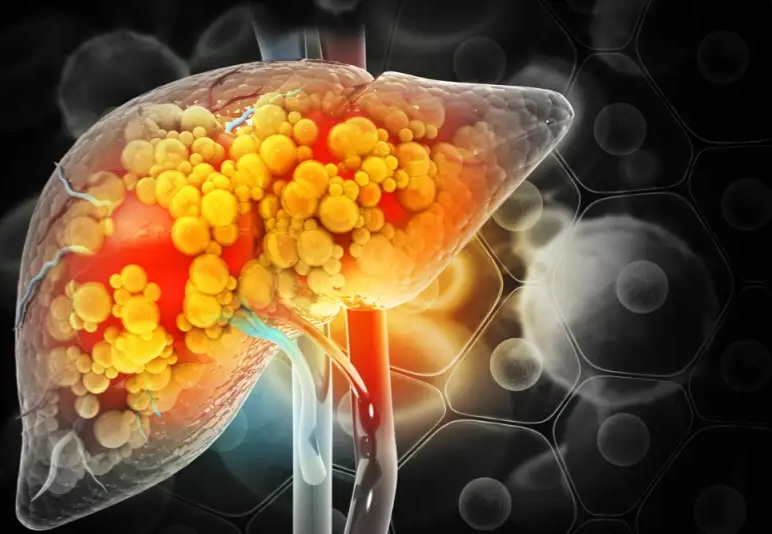

سرطان کبد یکی از دشوارترین سرطانها از نظر درمان است و در بسیاری از موارد در مراحل پیشرفته تشخیص داده میشود. علاوه بر این، جمعیت در معرض خطر این بیماری بسیار گستردهتر از آمار رسمی مبتلایان است. بیماری کبد چرب، سیروز، هپاتیتهای ویروسی و مصرف زیاد الکل از مهمترین عوامل خطر ابتلا به این سرطان به شمار میروند.

با توجه به شیوع بالای بیماری کبد چرب در جهان، هر راهکار ساده و قابل اجرا که بتواند خطر پیشرفت به سرطان کبد را کاهش دهد، از اهمیت ویژهای برخوردار است.

اما در افراد مبتلا به نارسایی یا آسیب کبدی، این فرآیند بهدرستی انجام نمیشود. در نتیجه آمونیاک در بدن تجمع مییابد. پژوهشگران در این مطالعه دریافتند که آمونیاک اضافی صرفاً یک ماده سمی بیاثر نیست، بلکه میتواند به سوختی برای رشد سلولهای سرطانی تبدیل شود.

به گفته پژوهشگران، این پرسش سالها مطرح بود که آیا تجمع آمونیاک صرفاً پیامد سرطان است یا خود بهعنوان محرکی برای پیشرفت تومور عمل میکند. نتایج این تحقیق نشان داد که آمونیاک میتواند بهطور مستقیم در تسریع رشد تومورهای کبدی نقش داشته باشد.